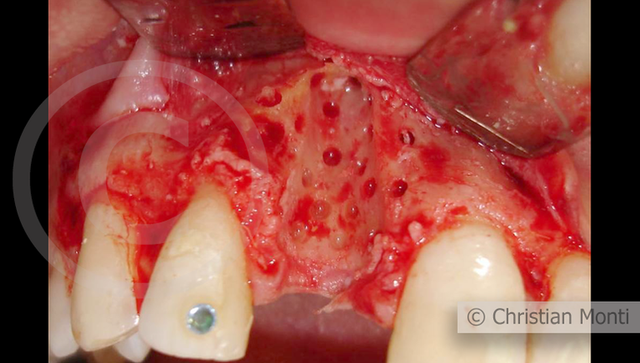

EDENTULIA SINGOLA

Impianto in sostituzione di un incisivo superiore